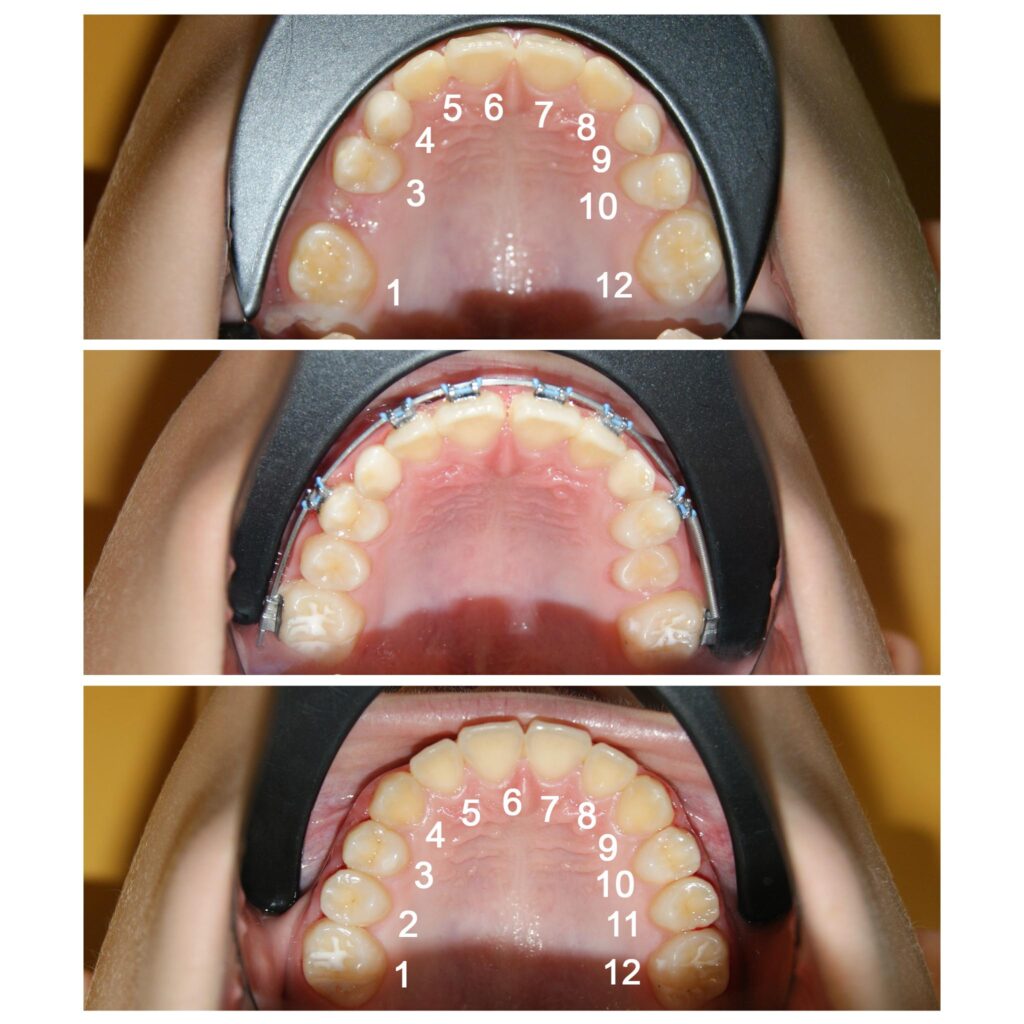

Recâștigarea spațiilor pierdute pentru dinții numerotați cu 2 si 11. Dacă nu am fi pus aparatul ortodontic fix dinții ar fi rămas blocați în intriorul osului, cu consecințe dramatice

Redeschiderea spațiilor pentru caninii definitivi (a se observa că pe o parte spațiul era închis complet)